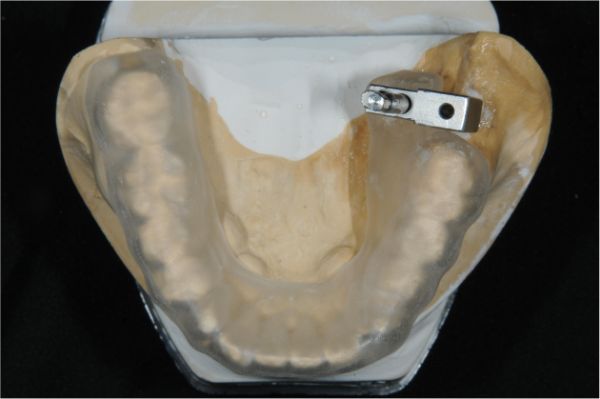

上咬合器製作模型

咬合器製作假牙